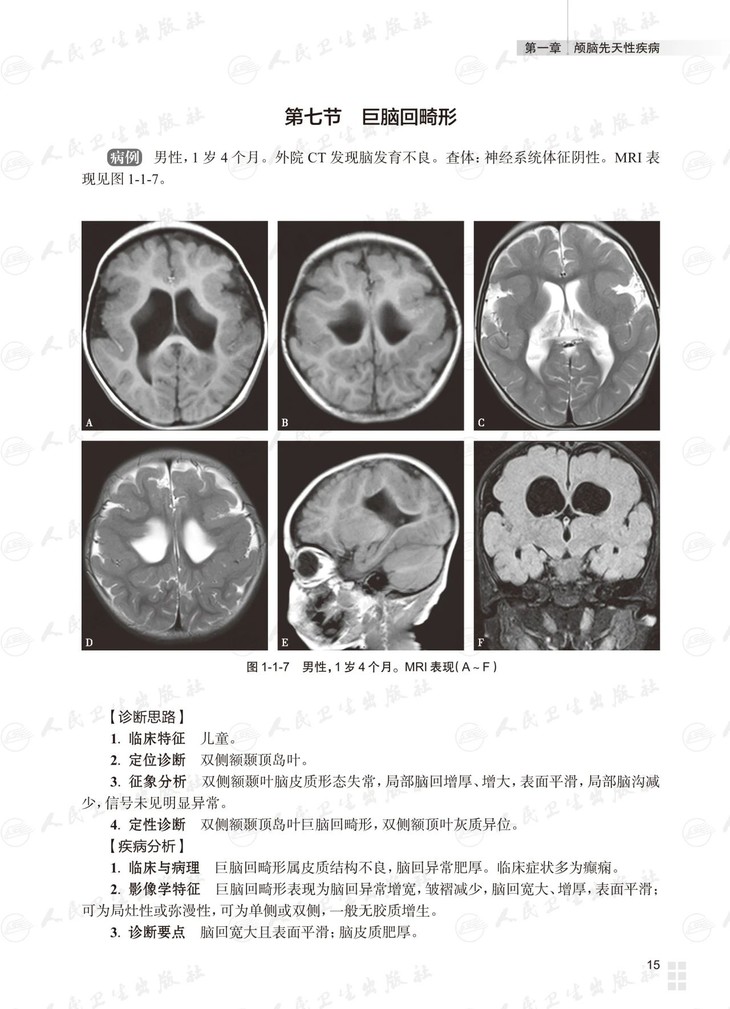

本书总论部分介绍多模态脑功能成像技术及临床应用。各论分为三篇:基础篇为常见颅脑疾病多模态磁共振成像典型病例分析,以复习为主,从疾病的临床与病理入手,解析影像学特征,提供影像诊断思路,最终给出诊断要点;进阶篇为各部位常见颅脑疾病多模态磁共振成像病例讨论,以考查为主,每章讨论颅脑同一部位的多个病例,附有多模态磁共振图像的征象分析、诊断及诊断要点,最后以思维导图的形式展示对该部位疾病的影像诊断思路;高级篇是多模态磁共振成像在颅脑疾病鉴别诊断中的应用,重在对功能成像技术进行横向比较,作出鉴别诊断。